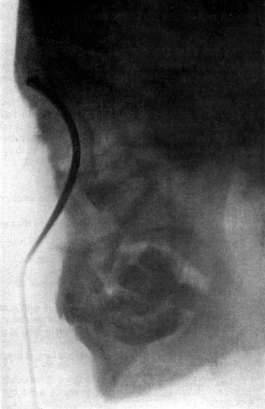

| 267. | Skiagram showing an Angular Tracheotomy Tube in the Trachea | 518 |

| 46. | Sims’s Vaginal Rest | 144 |

| 297. | Asch’s Cutting Scissors | 599 |